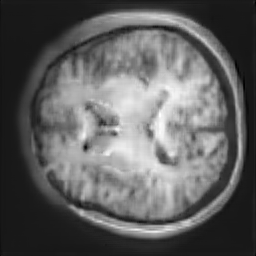

The study utilizes three 3D datasets, namely the GSP dataset[3], the LIDC-IDRI dataset[1], and the dataset employed for the Lung Nodule Analysis 2016 (LUNA16) challenge[21] which is a subset of LIDC-IDRI dataset. Samples from generated images at different stages of training are presented in Fig. 2 and Fig.3.

Figure 2: Synthetic images of CRF-GAN and HA-GAN at different iterations of training on GSP dataset